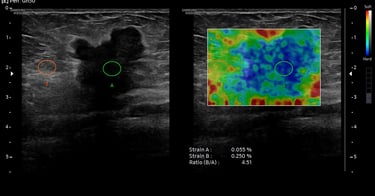

Nodul tiroidian - aspect ecografic sugestiv pentru malignitate - elastografia întărește suspiciunea

BIRADS 5 - tumoră mamară malignă - ecografic hipoecogenă, margini neregulate, halou hiperecogen, rigiditate crescută și SR crescut la elastografie